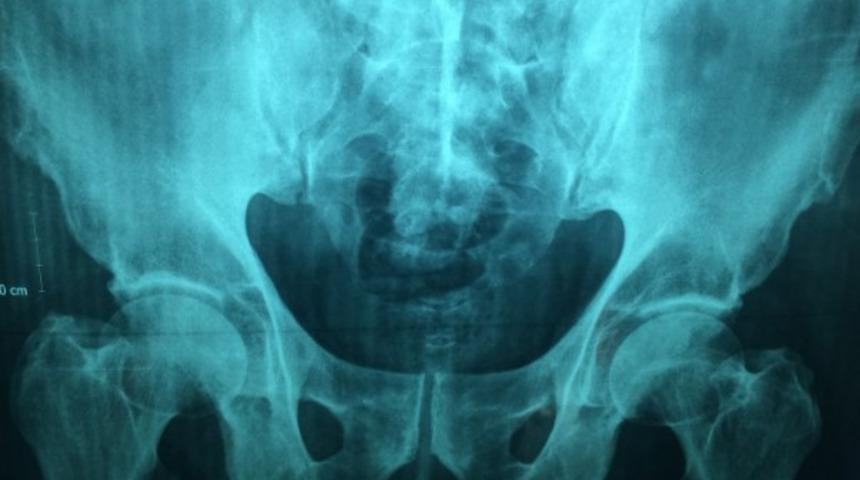

Öncelikle “Uyluk kemiği nedir?” sorusuna yanıt vererek başlayalım. Üst bacak kemiği olarak bilinen uyluk kemiği iskelet sisteminin en dayanıklı kemiğidir. Üst ucunda, pelvisin acetabulum adı verilen girintisi içinde eklem yapar. Üst bacağı diz kapağına ve kalça kemiğine bağlar.

Kalça ve baldır bölümünde bulunan uyluk kemiği leğen kemiğine bağlı ve kas dokusuyla örtülüdür. Ağrı oluşumu genellikle bu kas dokusunda meydana gelir. Fakat kırılmalar leğen kemiğinin işlevini yitirmesi ve bireylerin oturma ve kalkma hareketlerini kısıtlamasına sebebiyet verebilir. Uyluk kemiği problemleri genellikle sert bir yerden düşme veya yoğun egzersiz altında dokuların zarar görmesiyle gerçekleşir. İskelet sisteminde en uzun kemiklerden biri olan uyluk kemiği sorunları kişilerin hayatını direkt etkilemez sadece bacakların istendiği gibi hareket etmesinin önüne geçer.

Uyluk kemiği kırığı tespiti uzman hekim tarafından kolayca tespit edilir. Kırık oluşumunu gözlemlemek için kişiden bazı radyolojik görüntüler istenebilir. Daha sonra kırık hakkında tedavi yöntem şeması belirlenerek eskisi gibi yürüyebilme ve oturabilme fonksiyonlarını kazanmak hedeflenir. Kemiğin kırılma yeri, kaza sonucunda uğradığı şiddetin gücü ve yaş gibi faktörlere bağlı olarak uyluk kemiği kırığı iyileşme süreci için uygun tedaviye tabi tutulur.